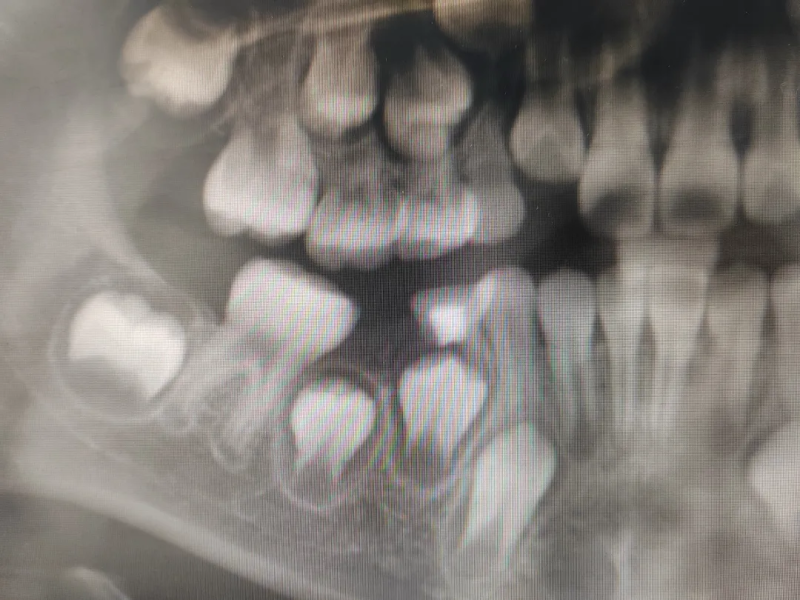

临床上由于严重的乳牙龋坏、牙髓炎等原因,会导致乳牙过早脱落、被拔除,或因外伤脱落等造成乳牙过早缺失。很多家长都不以为然,觉得反正恒牙迟早会生长出来,乳牙掉得早并不会有什么不良影响。但其实,乳牙对于牙齿、颌骨以及肌肉的发育至关重要,具有咀嚼、发音、美观、维持牙弓长度及促进颌面部正常发育的作用;同时乳牙作为天然的间隙保持器,可以很好地诱导恒牙正常萌出。乳牙龋坏、过早缺失会影响后续恒牙的生长,造成恒牙萌出困难、错位萌出等后果。而间隙保持器,除了能帮助稳固牙齿之间的距离,还能确保牙槽骨、颌骨及牙弓的正常生长发育,保持咀嚼及发音功能,维持正常的下颌运动和咬合关系,预防咬合紊乱的发生。